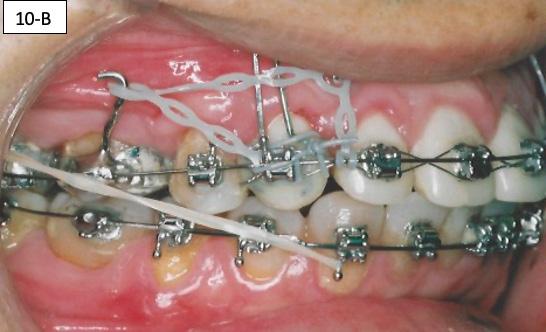

The side effect of protraction of the first molars is a mesiolingual moment (rotation). To neutralize this, the force must be applied, from the palatal aspect with the Power thread or the Elastomeric chain. The Power thread is attached to the lingual cleat of the molar bands, and it is stretched to the maximum, then tied to the arch wire between the cuspids and lateral incisors. A 3/16” – 4.5 oz Class III elastic was placed on the right side and a ¼”4.5 oz triangular elastic was placed on the left side to ameliorate the interdigitation (Figure 10-A, B, C).

FIG. oral mucosa FIG. 9C: Tissue guard, right lateral view FIG. 9D: Protraction of the first molar, left lateral view FIG. 10A: Lingual intra – Power thread, occlusal view FIG. 10B: Class II elastic, right lateral view FIG. 10C: Triangular elastic, left lateral view FIG. FIG. FIG. 12A: “W” with tail, right lateral view FIG. 12B: “W” with tail, left lateral view